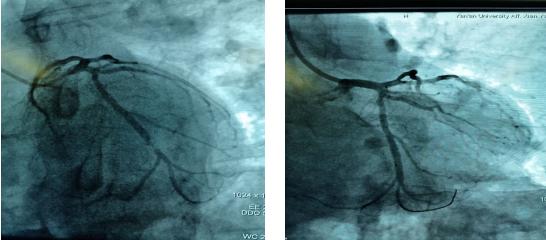

吳醫(yī)生迅速到達(dá)心電圖室,查看患者意識不清,心電圖提示下壁心肌梗死、三度房室傳導(dǎo)阻滯。立即給予阿托品、異丙腎上腺素提升心率,經(jīng)積極搶救后患者心律逐漸恢復(fù),意識逐漸清醒?!翱紤]患者是突發(fā)急性心梗引起的惡性心律失常,猝死風(fēng)險極高,必須行急診介入手術(shù)”,李新國責(zé)任總醫(yī)師告知家屬病情,同時啟動應(yīng)急預(yù)案,通知導(dǎo)管室做好急診手術(shù)準(zhǔn)備,應(yīng)急電梯待命…家屬同意手術(shù)后,立即前往導(dǎo)管室,實施急診冠脈造影手術(shù)。造影結(jié)果證實LCX中遠(yuǎn)段95%狹窄,術(shù)中于病變血管處植入支架1枚,術(shù)后血流恢復(fù),患者癥狀改善。在10余名醫(yī)護(hù)人員3個多小時的緊急搶救下,終于我們戰(zhàn)勝了死神。這一天,許久未晴的天空、陽光格外晴朗、明媚;這一天,北方的寒冬似乎也有了溫度…